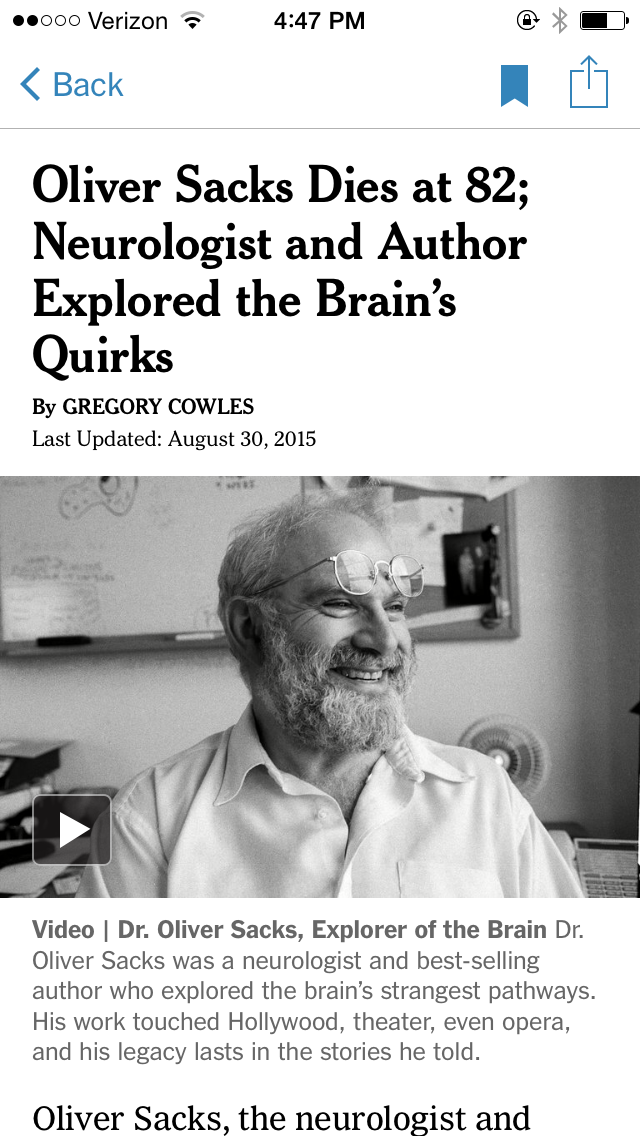

Let’s begin by going discussing one of the fantastic true stories told by the famous NYC neurologist, Oliver Sacks, who passed away just a few months ago and who weaved engaging clinical accounts and wrote a number of best selling books regarding cases of patients having extraordinary behaviors that resulted from strange or unknown neurological disorders including this one called The Man Who Mistook his Wife for a Hat. —>Indeed one of these accounts was about a man who actually mistook his wife’s face for a hat. This man, who was an accomplished musician and teacher at a school of music had developed trouble seeing faces and recognizing many types of objects in general as a result of degeneration in the visual system, likely from a stroke or something.

The patient (‘Dr. P’):

- good visual acuity & color vision

- good recognition of abstract geometric objects (cubes, spheres, etc)

- Trouble recognizing friends, family, pupils

- Trouble recognizing complex objects

Describing a rose: “About six inches in length. A convoluted red form with a linear green attachment”

Describing a glove: “A continuous surface, infolded on itself. It appears to have five outpouchings”

Let’s begin by going discussing one of the fantastic true stories told by the famous NYC neurologist, Oliver Sacks, who passed away just last summer and who weaved engaging clinical accounts and wrote a number of best selling books regarding cases of patients having extraordinary behaviors that resulted from strange or unknown neurological disorders including this one called The Man Who Mistook his Wife for a Hat. —>Indeed one of these accounts was about a man who actually mistook his wife’s face for a hat. This man, who was a well regarded and accomplished musician and teacher at a NY school of music had developed trouble seeing faces and recognizing many types of objects in general as a result of degeneration in the visual system, likely from a stroke.

This patient (let’s call him Dr. P)… was cognitively sharp, had good vis…

Hard time...

visual agnosia, prospognosia, lesion somewhere in temporal lobe of the cerebral cortex for reasons we will hopefully discover partially by the end of today’s class.

For him the visual world was a series of lifeless abstractions, seeing and describing the world almost the way a machine would see it without grasping the big picture.